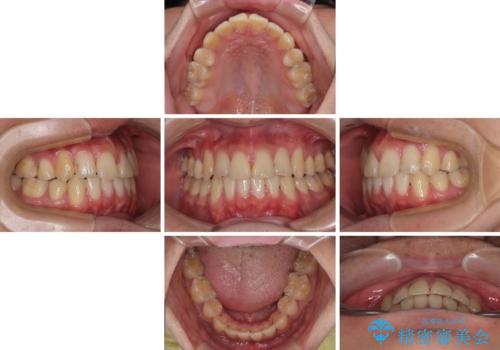

- 高校生の時に行った抜歯矯正の後戻りを気にして来院された患者様です。

インビザラインでの治療を希望されていて、デコボコの程度が中等度であり、安価なパッケージにて対応可能と判断されたため、インビザライン・モデレートを用いて矯正治療を行うこととしました。

- インビザライン・モデレート

- 10ヶ月

- 2-5回